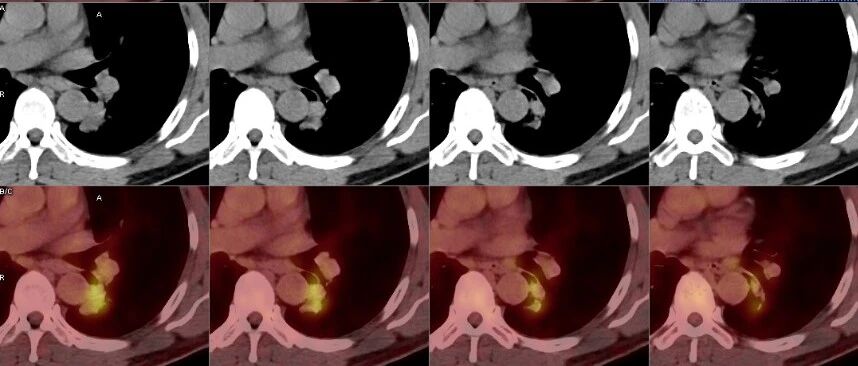

心外膜下的死神暗影:三次影像反转背后的肿瘤围城之谜